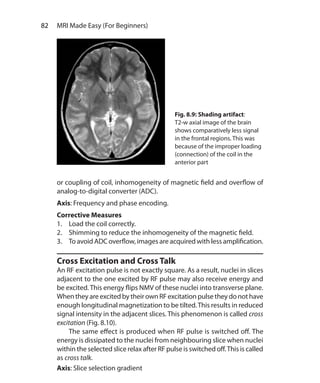

Shading Artifacts	 81

Cross Excitation and Cross Talk	 82